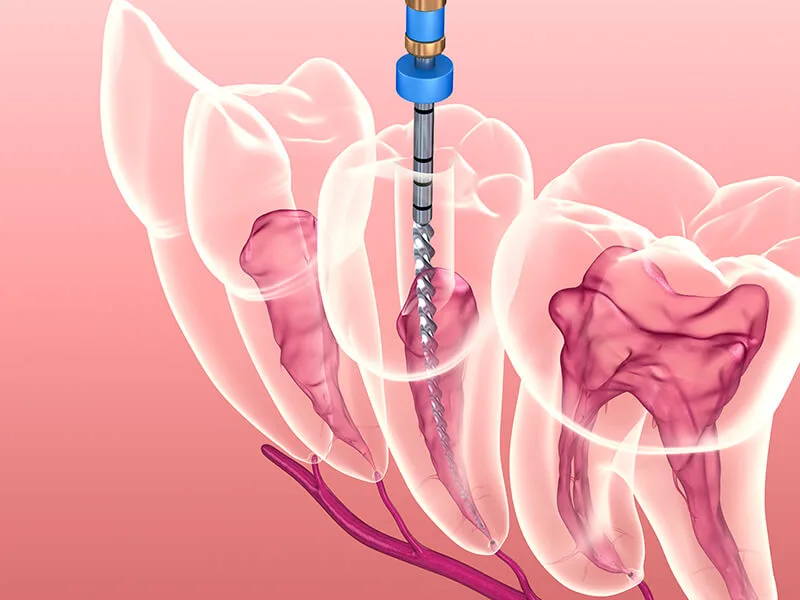

Tecnologia de Precisão: Uso de instrumentação rotatória e localizadores eletrônicos apicais;

Diagnóstico Milimétrico: Uso de radiografia digital para mapear as raízes com total clareza;